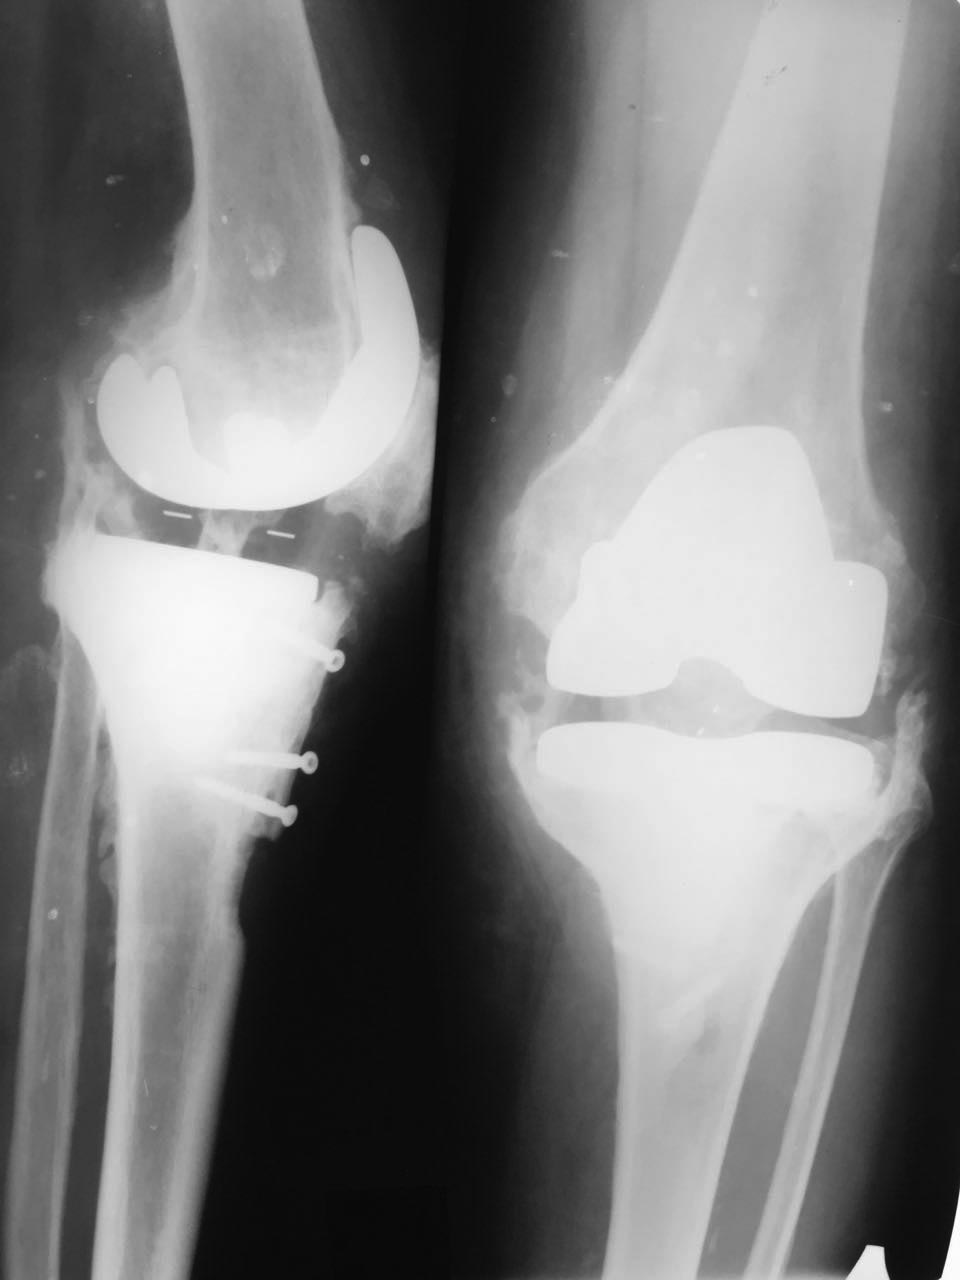

[Ortho] Рецидивирующие экзофиты после ТЭКС

Всем здравствуйте! Подскажите тактику, кто сталкивался с таким

явлением.. Протез стоит 10 лет, болей нет, но постоянно растут экзофиты.

Уже удаляли экзофиты 2 раза с хорошим, но временным эффектом. Сейчас

опять движения качательные. Спасибо!